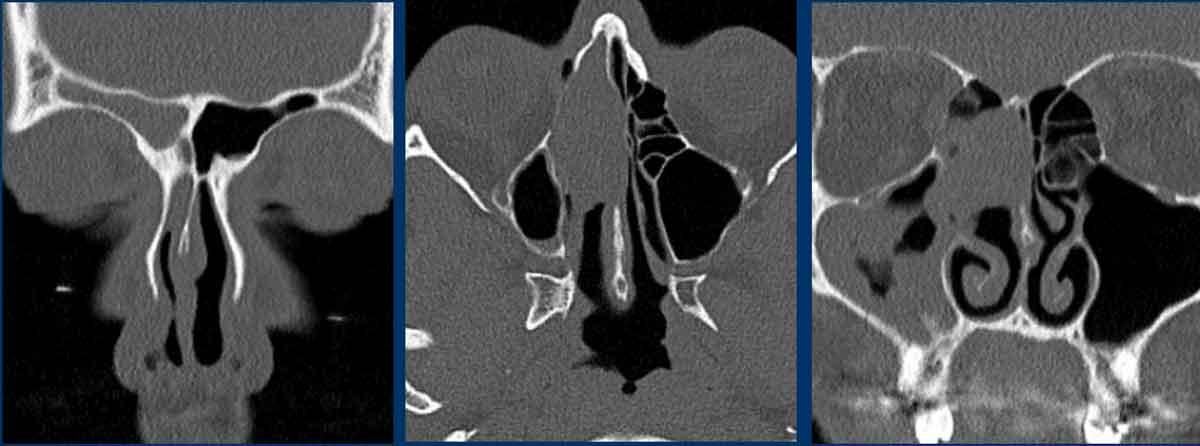

Bệnh nhân nữ 62 tuổi.

CT xoang được chỉ định bởi bác sĩ tai mũi họng. Thông tin lâm sàng: ‘viêm xoang một bên mạn tính’.

Hình ảnh

Có hình ảnh mờ đặc do mô mềm tại xoang hàm, xoang sàng và xoang trán bên phải (gọi là ‘kiểu tắc nghẽn phễu’).

Như đã đề cập, đây là một dấu hiệu cảnh báo.

Có hình ảnh thấu quang quanh chóp răng tại vùng chân răng hàm lớn trên bên phải, gợi ý nhiễm trùng răng (đầu mũi tên đen).

So sánh với bên trái bình thường trên ảnh cắt ngang (đầu mũi tên trắng).

Thăm khám lâm sàng bổ sung đã loại trừ tổn thương ác tính.

Bệnh nhân được chuyển khám răng hàm mặt vì nhiễm trùng răng hoàn toàn có thể là nguyên nhân gây viêm xoang mạn tính một bên.

Lưu ý: Vì lý do này, việc bao gồm vùng xương hàm trên trong trường chụp của CT xoang là điều hết sức quan trọng.